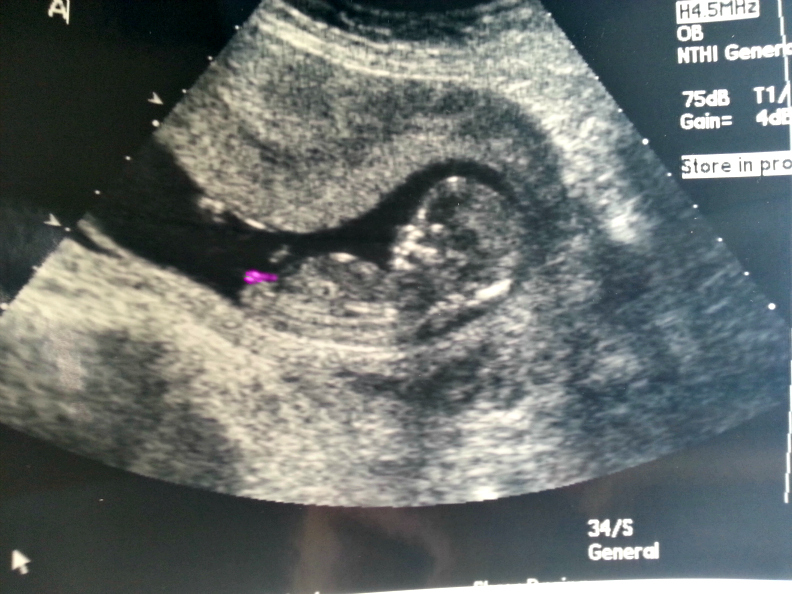

I was 12weeks 6 days and measuring 13weeks 3 days.

Attachment 23435

Maybe boy/girl. Not the best shots though!

I think B is a boy and A is a girl.

girl/boy just on skull, I am not good at nub. Hope your out of hospital soon.